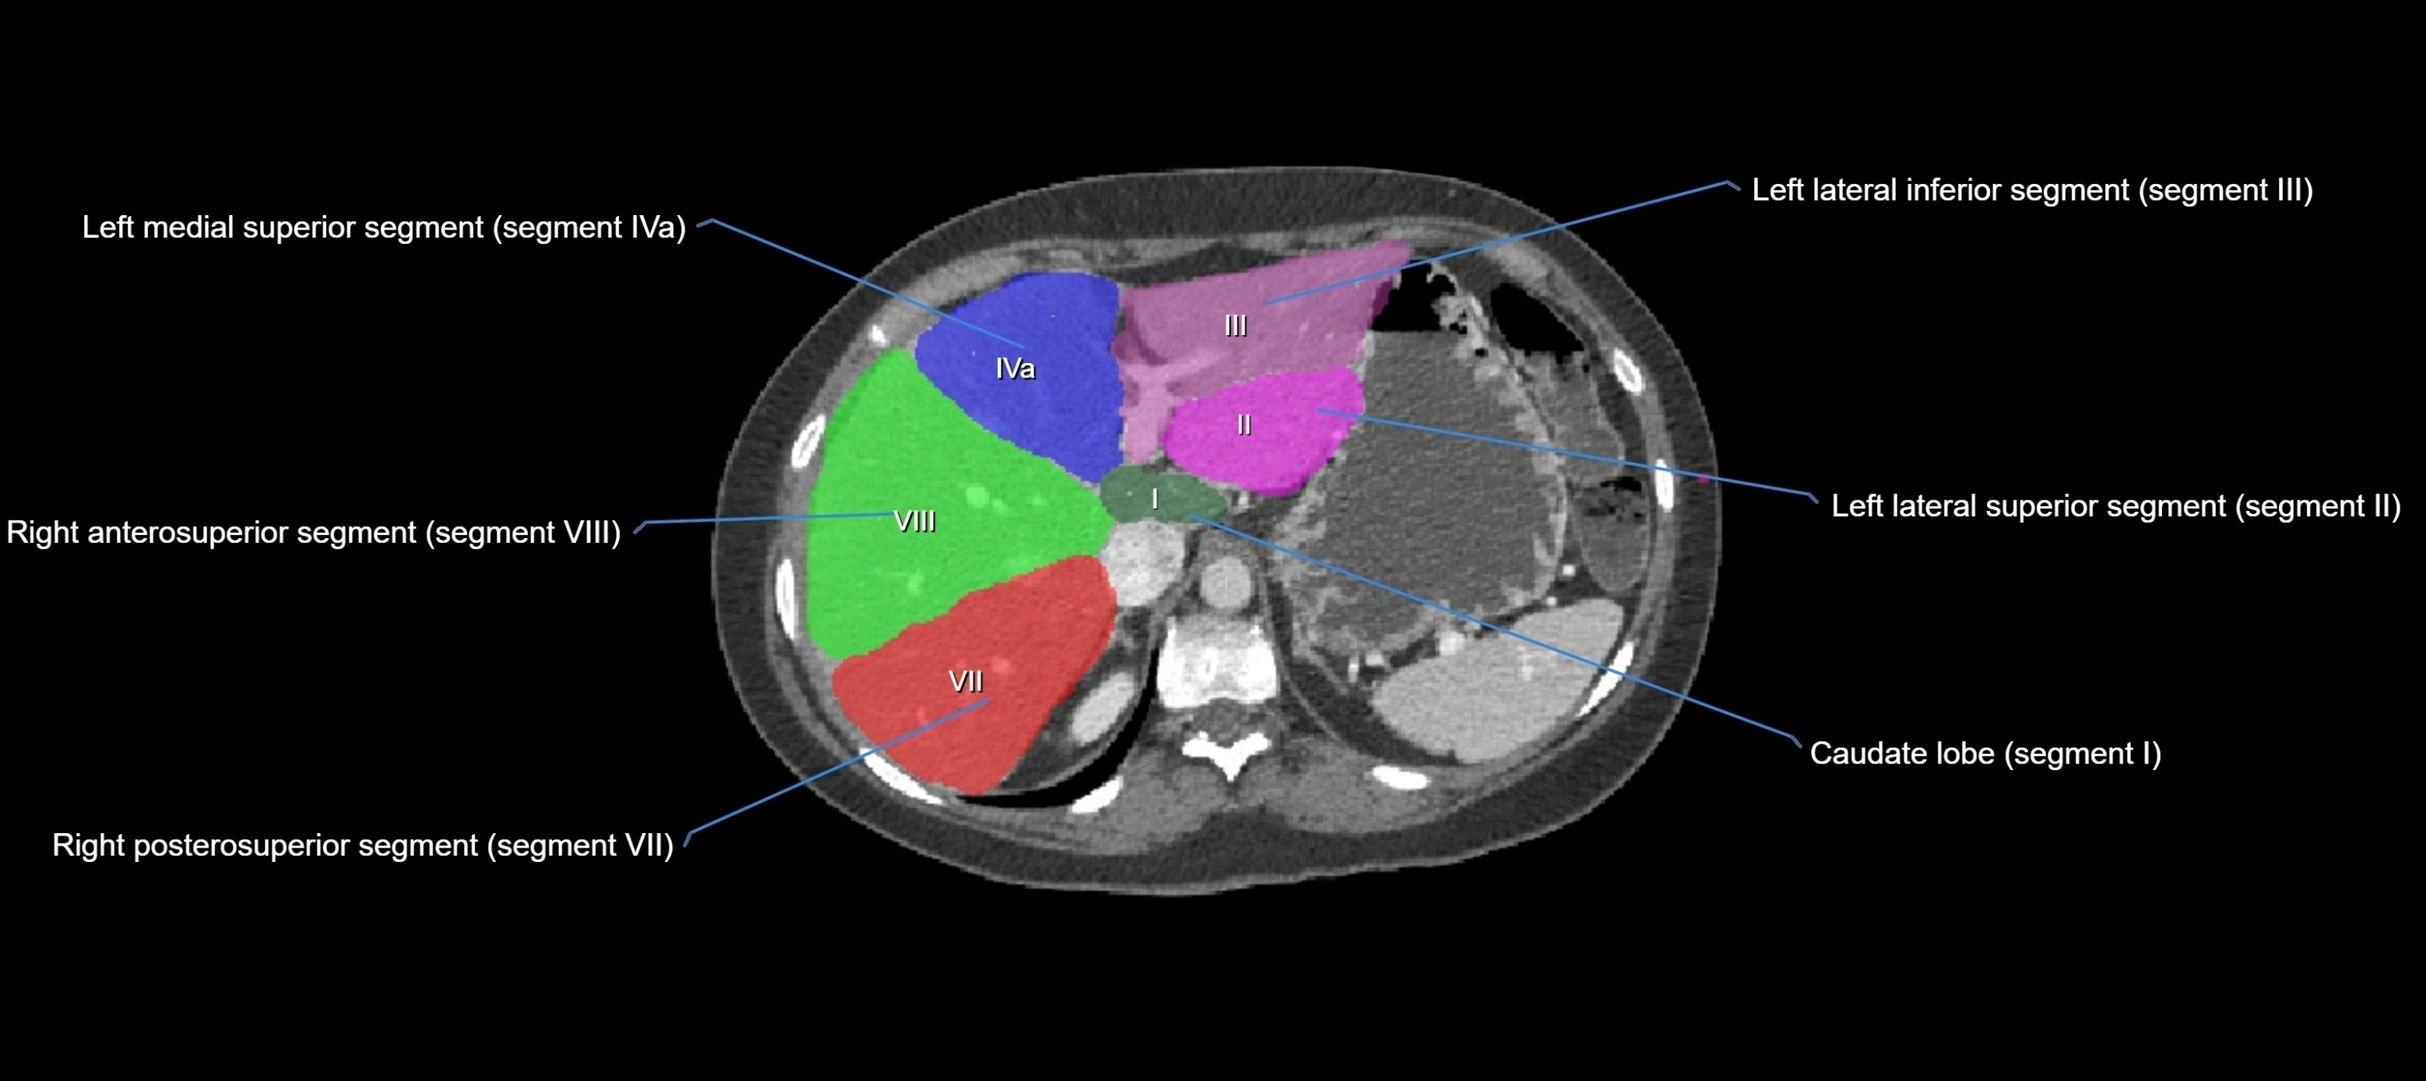

The caudate lobe of the liver is a distinct anatomical subdivision of the liver, designated as segment I in Couinaud’s classification. It lies on the posterior surface of the liver, between the fissure for the ligamentum venosum (left boundary) and the groove for the inferior vena cava (IVC) (right boundary). Superiorly, it is related to the posterior liver surface, and inferiorly it is separated from the left lobe by the porta hepatis.

The caudate lobe is unique because it receives dual portal venous and arterial inflow from both the right and left portal veins and hepatic arteries. It also has independent venous drainage directly into the IVC via multiple small hepatic veins, unlike other lobes that drain through the three main hepatic veins.

This anatomical autonomy makes the caudate lobe especially significant in liver surgery, transplantation, and hepatic venous outflow obstruction syndromes (e.g., Budd–Chiari syndrome). Enlargement of the caudate lobe is a characteristic imaging feature in chronic liver disease and cirrhosis.

CT Appearance

CT Pre-Contrast:

• Caudate lobe appears as a soft-tissue density, isodense to the rest of the liver

• Enlargement may be appreciated in cirrhosis or Budd–Chiari syndrome

CT Post-Contrast:

• Homogeneous enhancement in the portal venous phase, similar to rest of liver

• Independent venous drainage into the IVC may be visualized

• Lesions follow characteristic CT enhancement patterns (HCC: arterial hyperenhancement with washout; hemangiomas: peripheral nodular enhancement with centripetal fill-in)

CT Venous Phase (functional significance):

• Caudate lobe often enhances relatively more than other lobes in Budd–Chiari syndrome, due to preserved venous outflow

CT Image

image